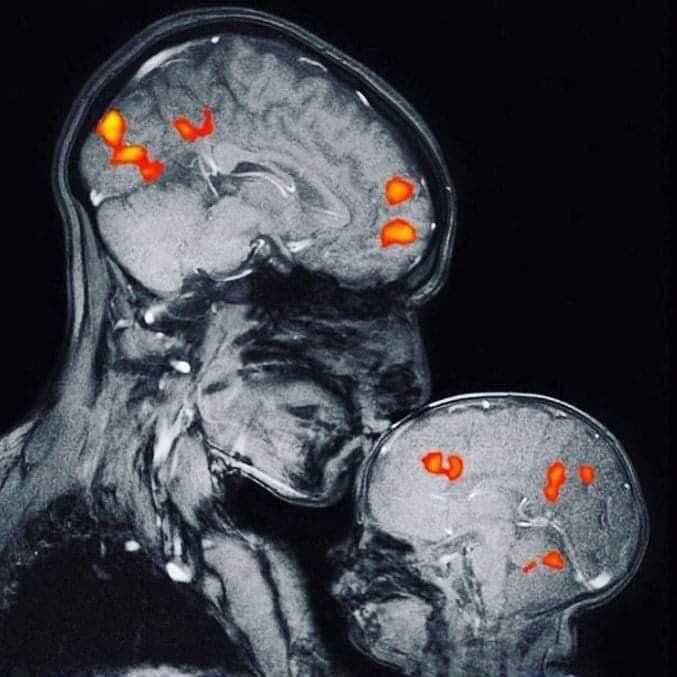

A mother kissing her baby. Her kiss has caused a chemical reaction in her son's brain which generates a burst of oxytocin - a hormone that generates feelings of attachment and affection. Credit: NH Neuro Training